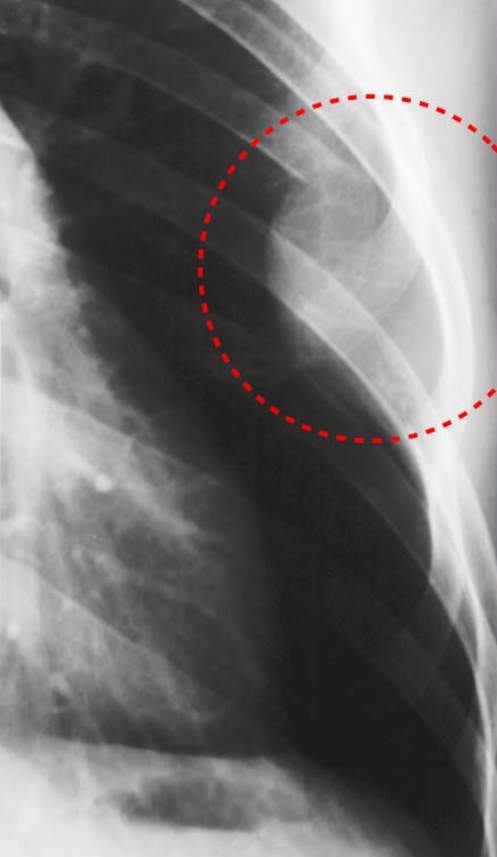

Figure2